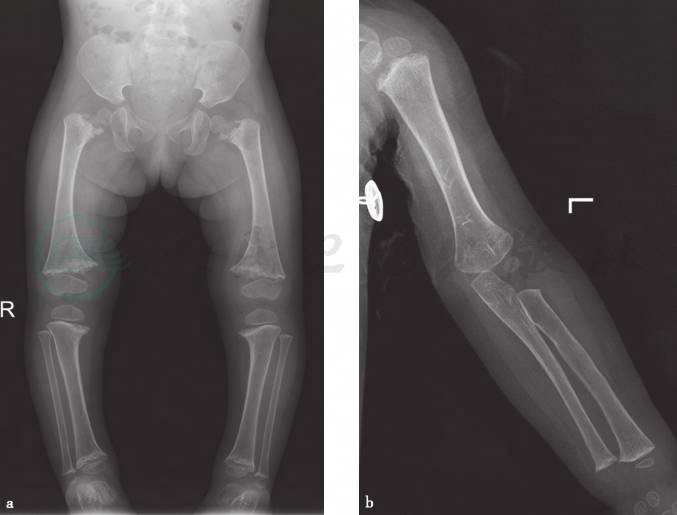

本病的主要X线特点:管状骨短粗,下肢比上肢明显,干骺端对称性膨大,可见不规则致密斑和囊状透亮区相互交错,骨骺和干骺端距离可加大,骨骺出现亦可延迟,但骨骺及骨干基本正常(图1)。

图1干骺软骨发育不良

X线片。a.双侧股骨及胫腓骨干骺端对侧性不规则膨大,先期钙化带毛糙,骨骺和干骺端距离加大,骨骺未见异常;b.左侧肱骨近端及尺桡骨远端干骺端改变较轻,远端骨骺未见异常